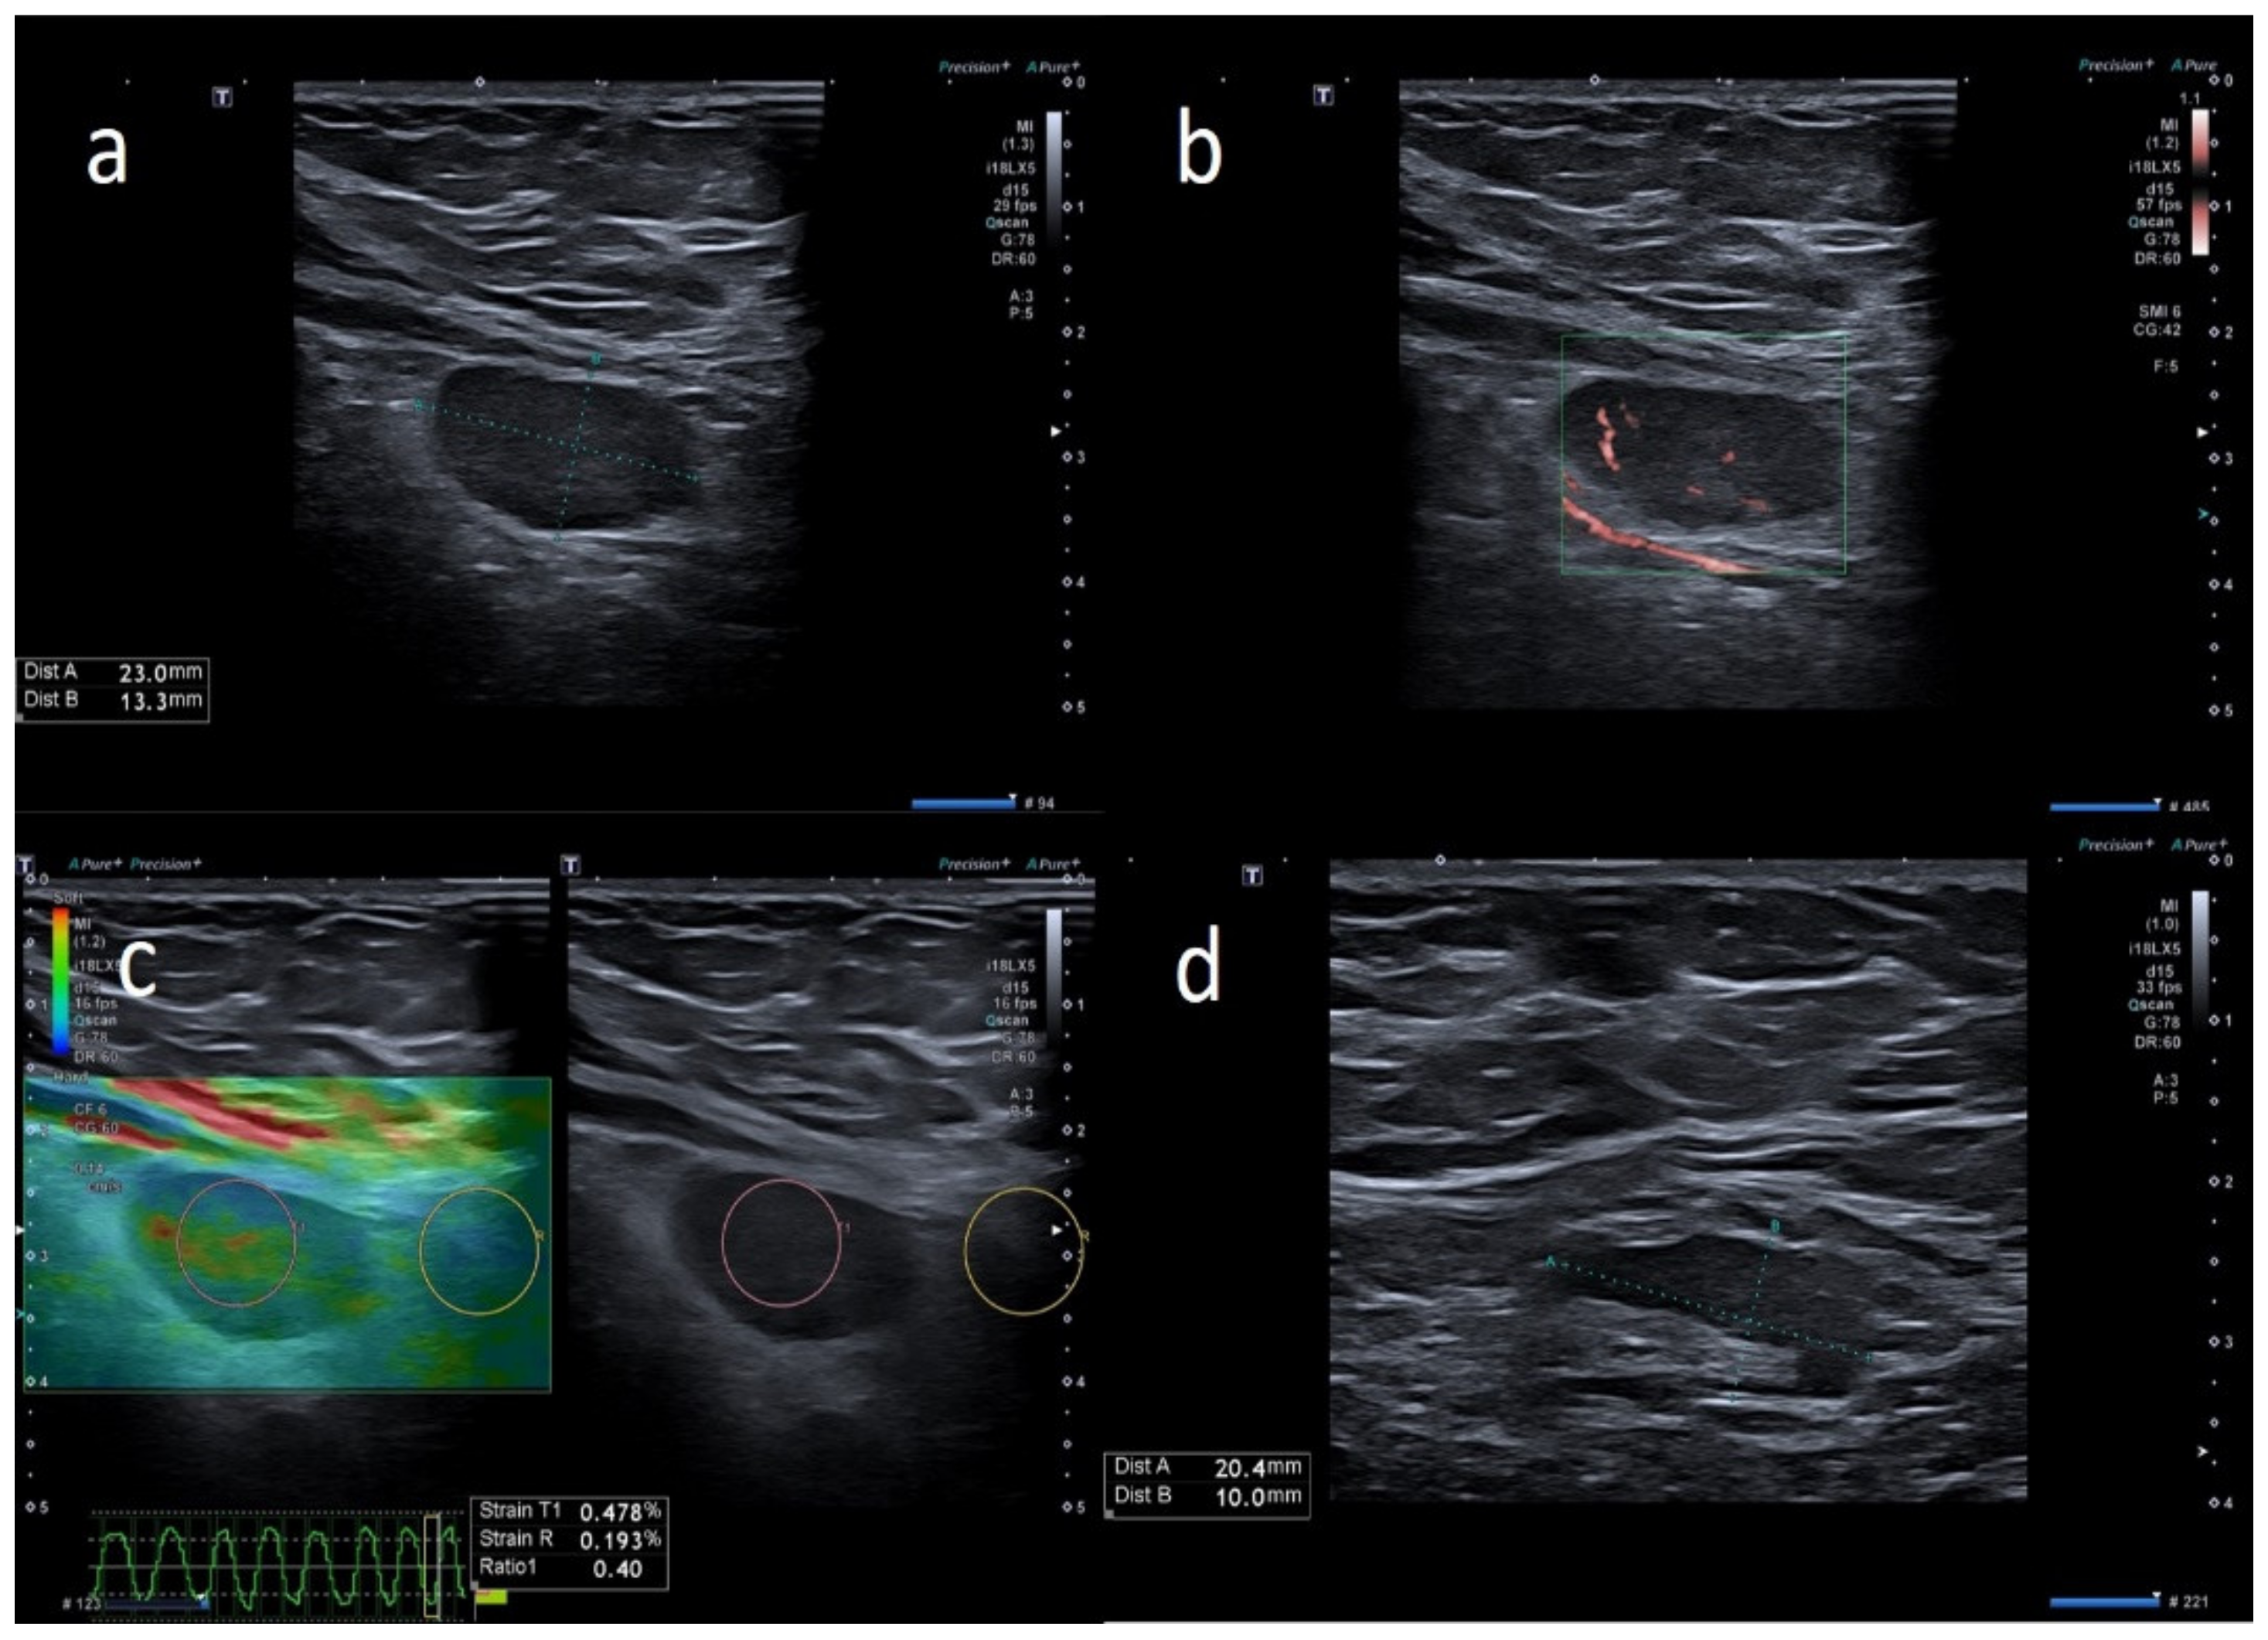

| W | 49 | Pfizer | Axillary ipsilateral to vaccine injection | Occasionally, 6 days after first dose, during breast sonography for oncological surveillance | Breast cancer 3 years ago | 4 | Variable: from 1.0 to 2.0 cm | Ovular | Asimmetric cortical thickening and poor evidence hilum | Stiffness similar to surrounding tissue | Central and peripheral vascular signals | Unnecessary other follow-up |

| W | 53 | Pfizer | Axillary ipsilateral to vaccine injection | Occasionally, 16 days after first dose, during breast sonography for oncological surveillance | Breast cancer 2 years ago | 3 | Variable: from 1.0 to 2.0 cm | Ovular | Asimmetric cortical thickening with hilum evidence | Stiffness similar to surrounding tissue | Normal | Unnecessary other follow-up |

| W | 37 | Pfizer | Axillary ipsilateral to vaccine injection | Three days after first dose vaccine, axillary swelling present | Melanoma 5 years ago | 5 | Variable: from 1.5 to 2.0 cm. | Ovular | Assimetric cortical thickening with hilum evidence | Prevalent hard pattern | Central and peripheral vascular signals | Normalized to 45 days |